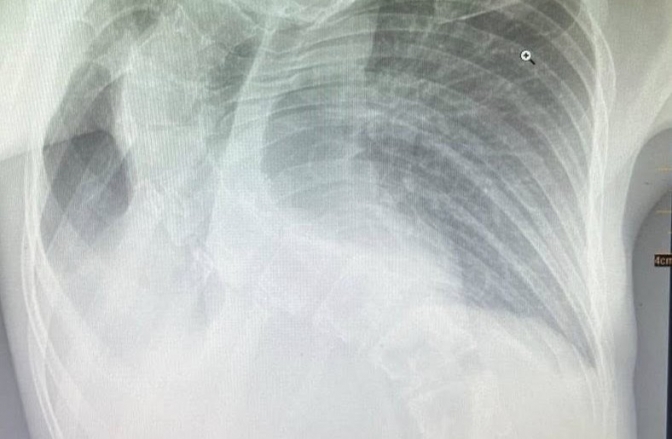

У Львові медики Центру дитячої медицини лікарні «Охматдит» врятували 13-річну дівчинку, у якої тривала пневмонія виявилася наслідком серйозного викривлення хребта. Дитина поступила до лікарні у важкому стані — з утрудненим диханням, слабкістю та поганими результатами обстежень.

Як розповіли в медзакладі, під час ультразвукового дослідження легень лікарі побачили велику ділянку ураження, яка зберігалася незважаючи на покращення загального стану та аналізів крові. Повторні УЗД не показували динаміки, що викликало підозру на іншу причину ураження.

Розв'язку ситуації принесла комп’ютерна томографія: обстеження виявило значну деформацію грудної клітки через сколіоз. Хребет був настільки викривлений, що буквально здавлював одну з легенів, що й спричинило не лише запалення, а вже й хронічні фіброзні зміни в тканині – тобто незворотні ураження.

«За словами мами, деформація хребта почала проявлятися приблизно з 10 років. Але ми розуміємо, що цей процес стартував ще раніше – просто на той момент не було зовнішніх ознак. Через складність стану довелося залучити фахівців різних напрямків», – пояснила педіатр-алерголог Центру Руслана Проць.